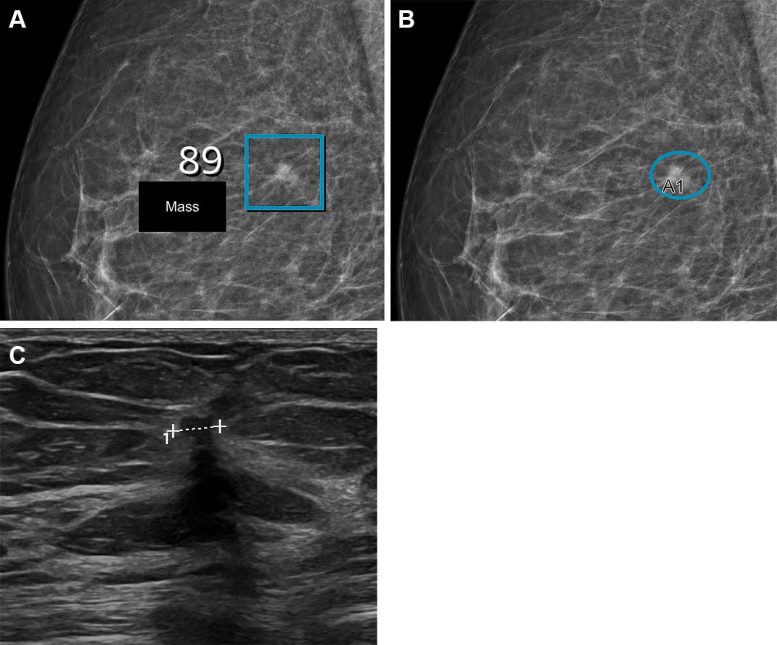

תמונות של אישה שהייתה לה צפיפות דיווח הדמיית שד ומערכת נתונים של 2 והייתה בת 57 כאשר עברה בדיקה עם מערכת הבינה המלאכותית (AI). ת ההקרנה קיבלה ציון גבוה של בדיקת AI של 10 בהתבסס על נגע זה עם ציון של 89 מתוך 100. (ב) אותה תמונה כמו ב-A, אך עם ממצאים של הרדיולוגים. בגלל הציון הגבוה של בדיקת AI, ההקרנה נקראה פעמיים על ידי שני רדיולוגים, שסימנו את אותו נגע (סגלגל, A1) כמו מערכת ה-AI, מה שהוביל להיזכרות. (ג) תמונת ארה"ב חתוכה מראה קרצינומה פולשנית קטנה (4 × 7 מ"מ) (קו) שנצפתה במהלך בדיקת האבחון. קרדיט: האגודה הרדיולוגית של צפון אמריקה (RSNA)